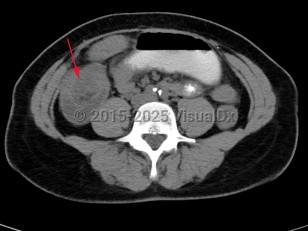

Intussusception is a telescoping or invagination of a part of the intestine into the lumen of an adjacent segment. Intussusception can present with variable severity. It can present with bowel ischemia and perforation with need for emergent surgical intervention, or it can present as relaxing / remitting abdominal pain of unclear etiology with intermittent symptoms and no signs of systemic illness. Jejunojejunal, jejunoileal, ileoileal, ileocolonic, and colocolonic are all types of intussusception that can occur, with the majority involving the small intestine.

Intussusception in adults presents with similar symptoms: sudden-onset abdominal pain that can relax and remit, with or without symptoms of acute bowel obstruction and hematochezia. Intussusception in adults can also be caused by viral infections, polyps, or postsurgical adhesions, but there is greater concern for underlying malignancy – either small or large bowel or extrinsic (eg, lymphoma) – as a trigger point.

Initial management requires ensuring hemodynamic stability, as many patients are dehydrated, and assessing concern for bowel perforation, which could require broad-spectrum antibiotics and urgent surgical intervention. Air or barium enemas can be both diagnostic and therapeutic. However, intussusception will frequently recur, in which case surgical resection is often required. Further imaging (ie, small bowel x-ray series, CT or MRI abdomen) can be utilized to identify the etiology if it is unknown based on presenting symptoms and a barium / air enema.